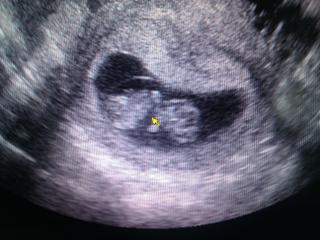

taaaaaaaakze... krpec nam rastie ako z vody 😵 podla ms som dnes 9 +0, podla utv 9+5 🙂 srdiecko bilo o 106 😵 krpec sa hybal, reagoval na lekarku, ked sa ho snazila prinutit viac k cinnosti 😀 ale ked prisiel manzel dnu, aby videl krpca, tak ako na povel prestalo 😀 ale manzel povedal, ze nejaky pohyb zachytil, ale vela nie. potom sa krpec uz odmietol pohnut 😀 fotku mame z mobilu... ale to najdolezitejsie vidno 😉 ta zlta vec je myska... lekarka ukazovala manzelovi, kde je srdiecko 🙂 07.02. mame poradnu a tam uz dostaneme aj tehu knizku. konecne 😀 aha a este rozmery... jedno bolo 2.7 a druhe 4.3... len uz neviem, co je dlzka a co vaha 😀